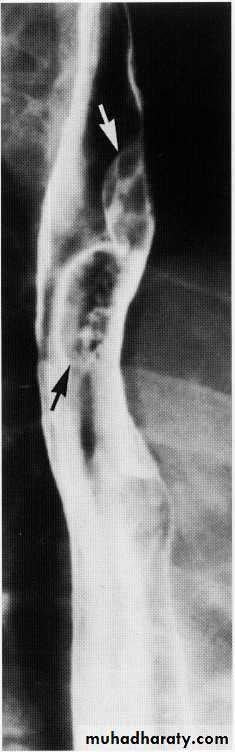

Advanced esophageal Ca